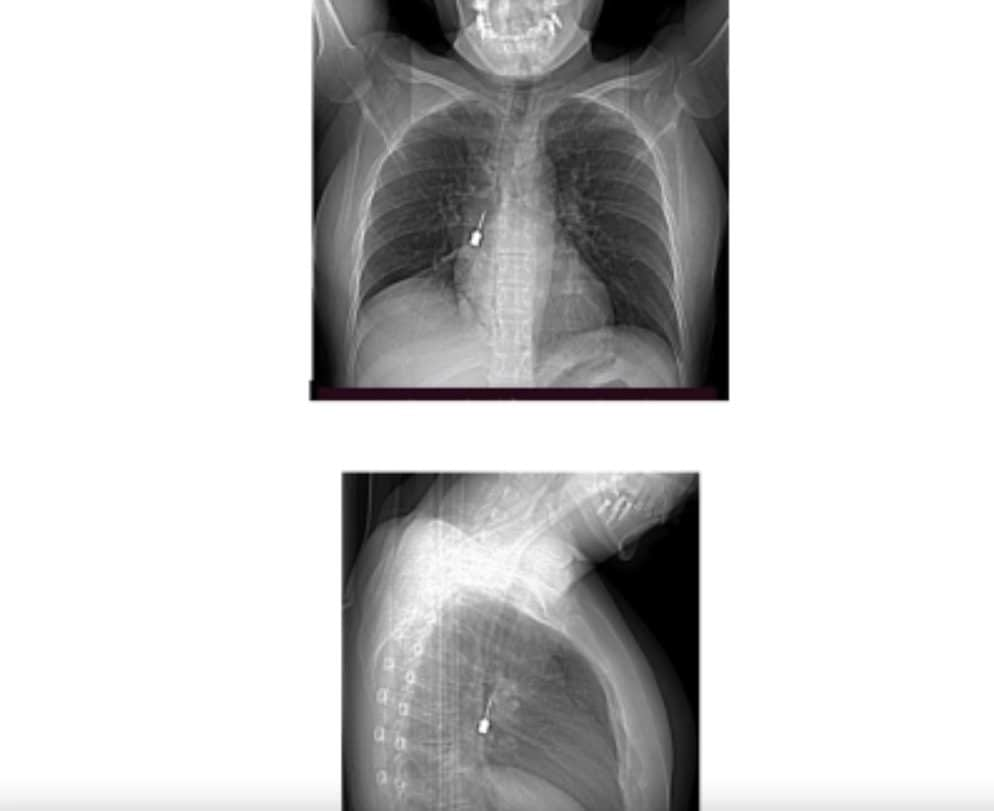

Come si vede dalle foto diffuse dallo stesso ospedale reggino, la Tac infatti mostrava chiaramente la presenza di un corpo estraneo metallico pericolosamente incastrato nel bronco lobare inferiore del polmone destro. Allo stesso tempo i medici si sono accorti anche di “un concomitante pneumomediastino” ossia la presenza di aria nello spazio compreso fra i due polmoni. Una situazione molto delicata e pericolosa che ha spinto i sanitari a disporre una immediata operazione chirurgica d’urgenza.

Gli specialisti hanno provveduto a una delicatissima procedura endoscopica effettuata dal Direttore dell’UOC di Chirurgia Toracica, il dottor Baldassare Mondello, insieme alla sua équipe medica e agli anestesisti. L’intervento è perfettamente riuscito con l’estrazione per via broncoscopica del corpo estraneo. Si è scoperto così che si trattava di un piccolissimo cacciavite odontoiatrico che in qualche modo era stato accidentalmente inalato dalla giovane paziente.